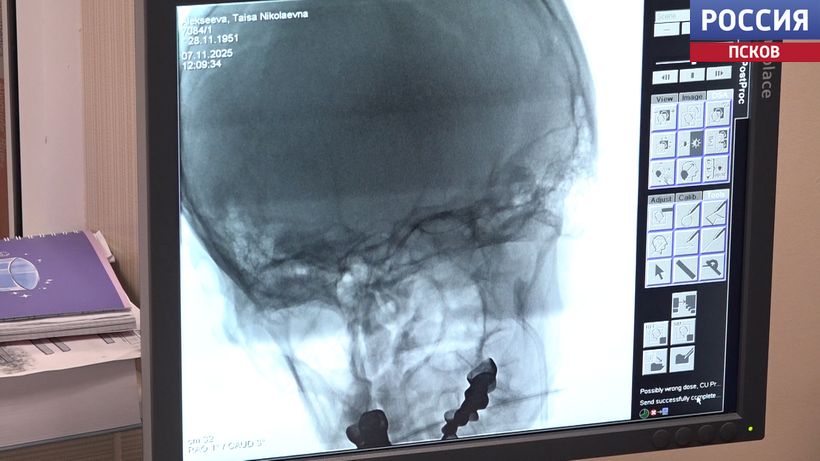

Оперативная медпомощь на высоком уровне. Так оценил работу Великолукского филиала областной больницы Сергей Леонов. Депутат Государственной Думы от фракции ЛДПР во время региональной недели посетил терапевтический корпус, где расположен региональный сосудистый центр. Репортаж Ларисы Чуриковой.

Так оценил работу Великолукского филиала областной больницы Сергей Леонов. Депутат Государственной Думы от фракции ЛДПР во время региональной недели посетил терапевтический корпус, где расположен региональный сосудистый центр. Репортаж Ларисы...